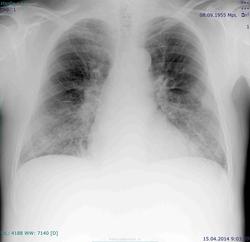

Страдает бр астмой, 1955 г.р., повышение температуры до 39 градусов, есть ли пневмония (2-сторонняя н\долевая?)?

я бы смело написал 2-сторонняя н\долевая пневмония

Саркоидоз бегом исключайте!

Вы просто описываете эту картину как диссеминированный процесс, лимфааденопатию под знаком "?", т.к. при бронхиальной астме бывают такие корни и без увеличенных л/у. А дальше клиницист уже разберется, что-куда.Может, и пневмонию сначала полечит.

Сомнительные пневмонии.

Что в анализах крови? Пневмонии не видно. Есть усиление легочного рисунка. Усиление легочного рисунка с 2009 года для БА не характерно, возможно прогрессирование диффузного интерстициального процесса. Наверное нужно КТ в динамике.

Контроль, наверное, все же пневмония.

Не факт. Саркоидоз нельзя исключить.